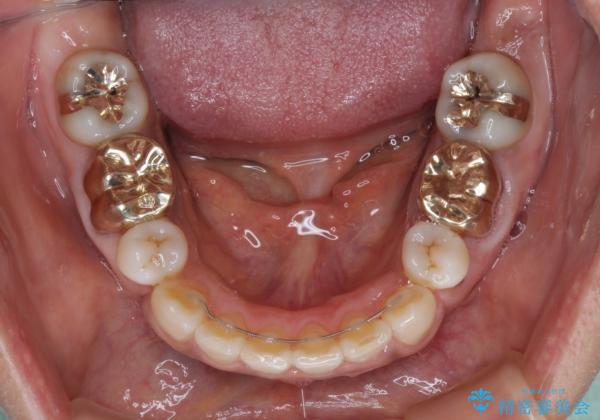

奥歯の銀歯をゴールドに

- 矯正治療後に、下顎奥歯の銀歯をすべてゴールドにすることを希望された患者様です。

セラミッククラウンやセラミックインレーによる補綴治療も提案しましたが、お友達にゴールドを自慢したいとのことで、ゴールドクラウンとゴールドインレーにて処置することとしました。

ゴールドは「白い歯」ではありませんが、銀歯の金属色とは異なり、非常にきれいな色合いが特徴です。

もちろん、適合が極めて良いという圧倒的メリットもゴールドクラウンやゴールドインレーの特徴です。